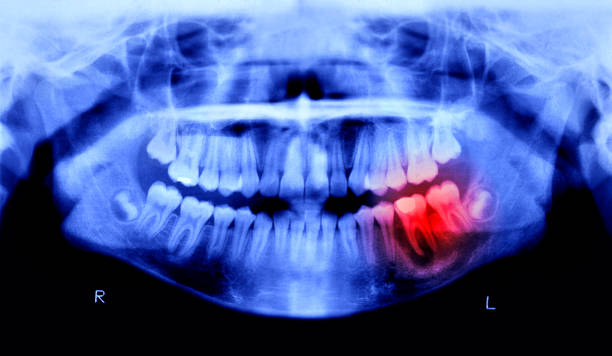

Digital X-Rays & Intraoral Imaging

Quick, low-radiation diagnostics to identify cavities, infections, and bone loss—often before they become visible to the naked eye.